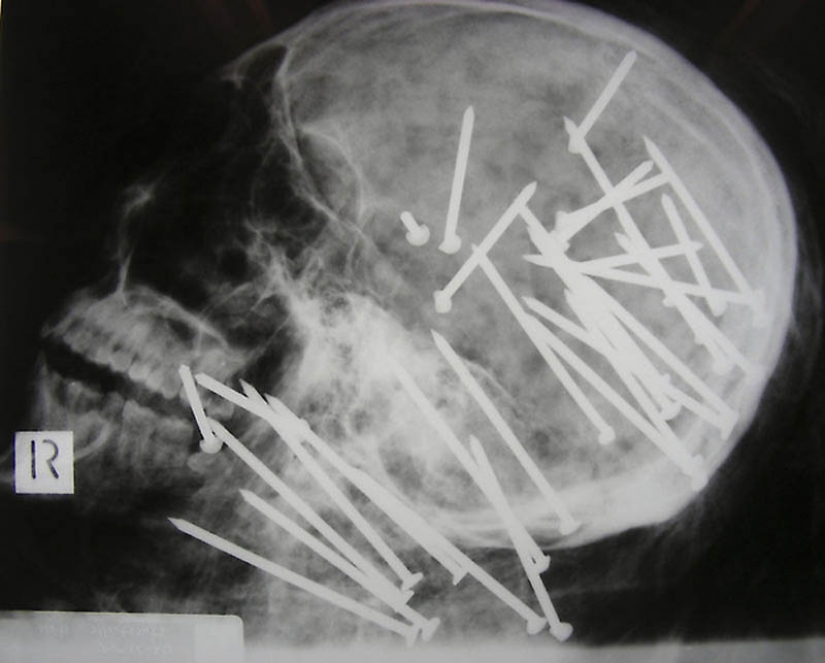

1. The skull of a Chinese man who was shot in the head with a pneumatic hammer

13. The nail in the human skull – the patient accidentally shot himself with a pneumatic hammer. He didn't even know that shot himself with a 10 – meter nail was found only after 6 days.